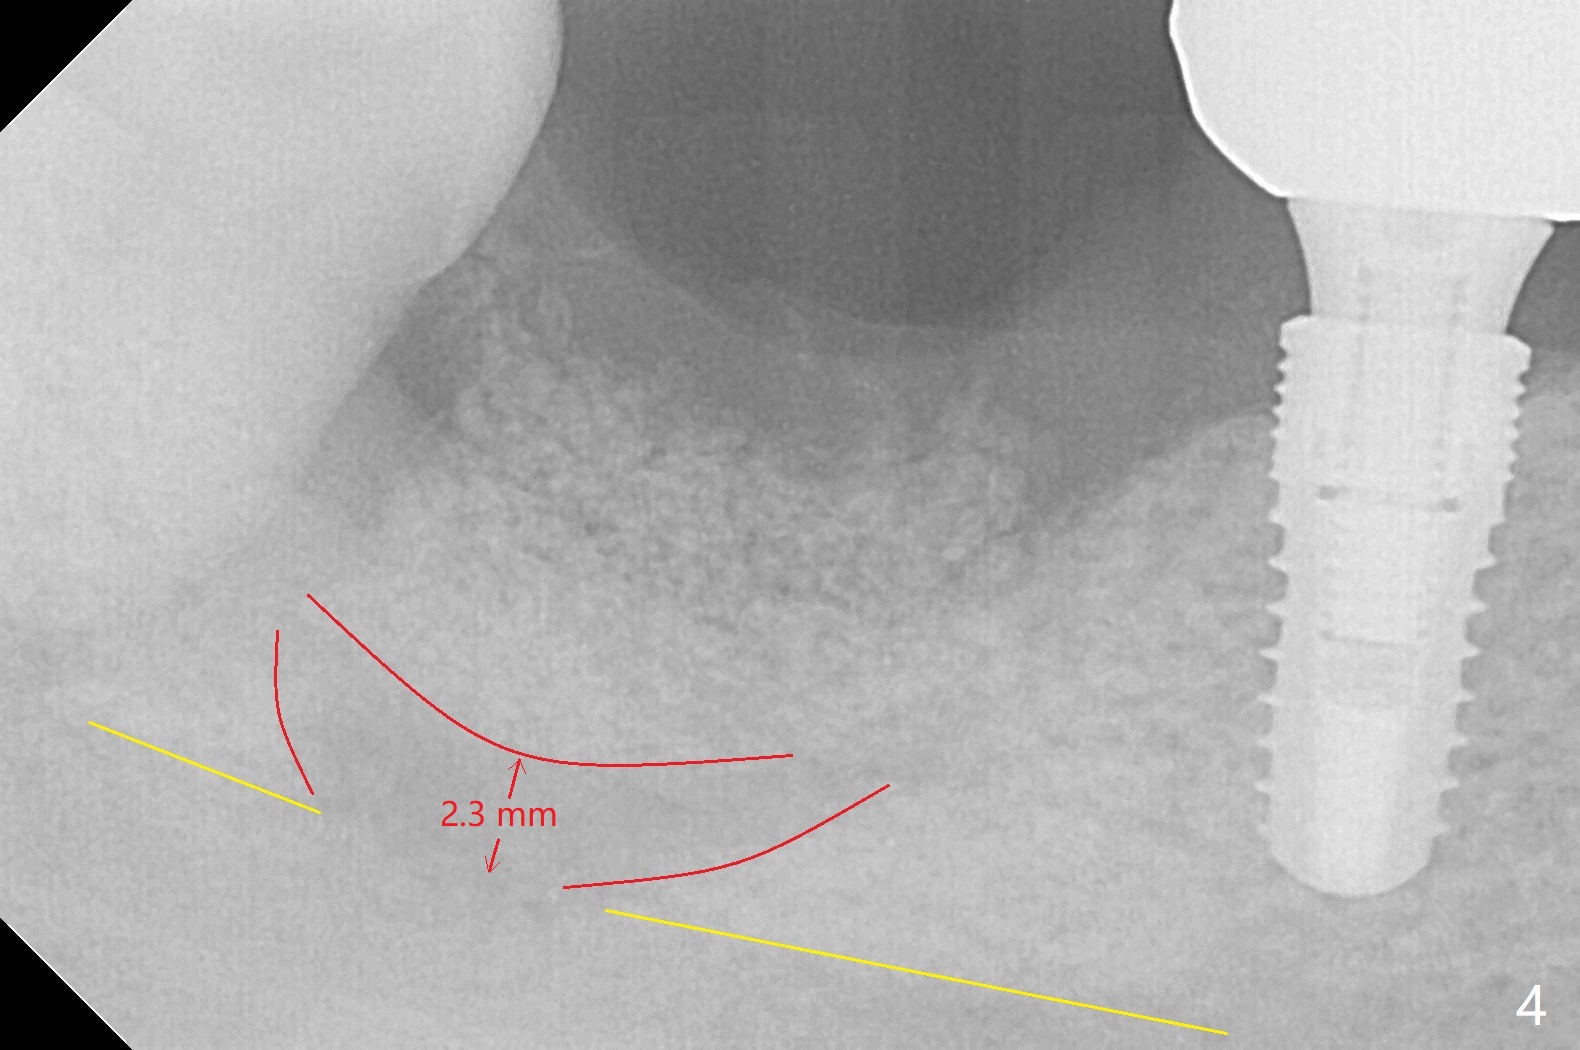

Although the bony socket is shallow, the soft tissue one remains deep at #31 with gingival recession (Fig.1 *). The deep soft tissue socket with hemorrhage after extraction presents difficulty in debridement of granulation tissue apically. After placement of allograft (Fig.3 *) and overlying collagen membrane (Fig.2 C), the socket is closed with 4-0 Chromic gut suture. In fact, there is ~ 2 mm granulation tissue left (Fig.4 red (yellow line: upper border of the Inferior Alveolar Canal)). To reduce socket shrinkage, the tooth #32 is not extracted. The collagen membrane has lost 1 week postop (Fig.5). More sutures should have been used, preferably using Human Amnion Chorion Allgraft as a membrane. The latter promotes wound healing. The bone graft also seems to have lost in 8.5 months (Fig.6). A short implant will be placed mesially and obliquely (Fig.7).